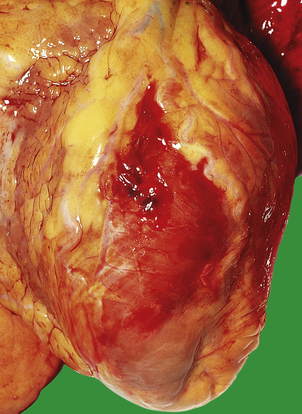

Malignant hypertension

Malignant hypertension is a clinical and pathological syndrome. The characteristic features are a markedly raised diastolic blood pressure, usually over 130–140 mmHg, and progressive renal disease. Renal vascular changes are prominent, and there is usually evidence of acute haemorrhage and papilloedema (Fig. 13.11). Malignant hypertension can occur in previously fit individuals, often black males in their third or fourth decade. However, most cases occur in patients with evidence of previous benign hypertension; this is sometimes termed accelerated hypertension.

The consequences of malignant hypertension are:

cardiac failure with left ventricular hypertrophy and dilatation

blurred vision due to papilloedema and retinal haemorrhages

haematuria and renal failure due to fibrinoid necrosis of glomeruli

severe headache and cerebral haemorrhage.

The characteristic histological lesion of malignant hypertension is fibrinoid necrosis of small arteries and arterioles (Fig. 13.12). The kidney is frequently affected and some degree of renal dysfunction is inevitable. Occasionally there is massive proteinuria, and renal failure develops. Acute left ventricular failure can occur.